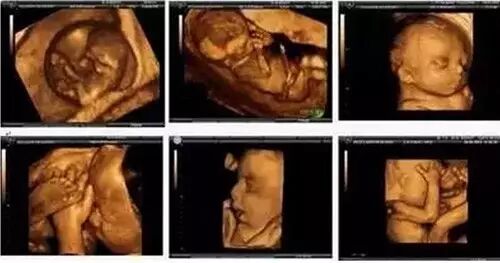

四维彩色超声诊断仪是目前世界上最先进的彩色超声设备。其结果是:能够显示您未出生的宝宝的实时动态活动图像,或者其它人体内脏器官的实时活动图像,多方位、多角度地观察宫内胎儿的生长发育情况,且可以为早期诊断胎儿先天性体表畸形和先天性心脏疾病提供准确的科学依据。

韩国麦迪逊四维彩超拥有出色的人体工程学设计,不存在射线、光波和电磁波等方面的辐射,对人体的健康没有任何影响

做四维彩超的最佳时间为怀孕5-7(20-28周)个月,因为这个时段胎儿的肢体及各主要脏器已经全部发育,而且羊水适中,骨骼回声影响比较小,图像清晰,因此这个时期是进行胎儿畸形检测最为理想的时期,检查可排除大部分的畸形。但因孕妇的个体差异,个人的具体时间还请和医生联系,按医嘱时间定。